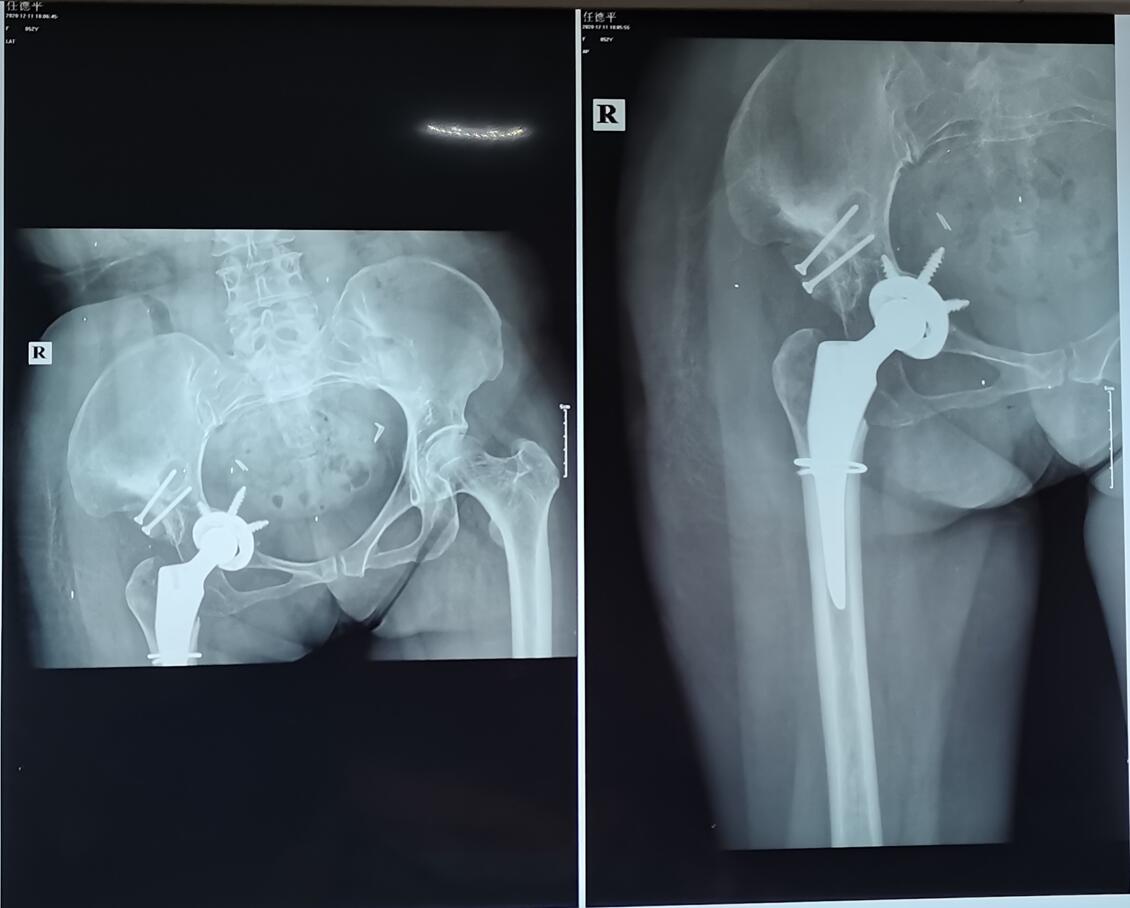

2020年11月25日,该医院对我进行手术治疗,手术名称:右侧人工全髋关节置换手术及造盖成形术、植骨术。结果手术失败了!下面是我手术前后的图片。

如果不是专业人士来发现我的问题,估计我现在都还蒙在鼓里;由于我这个是股骨头坏死,所以需要用假体来替换,但是这家医院技术水平太差,导致这个假体安装位置不正确;从片子中看,假体有部分已经进去了盆腔,甚至在盆腔里还能看见两个耀眼的长钉子,请问这家医院的手术医生究竟要干什么!?盆腔里有大量的脏器、血管、膀胱等等重要的东西,有没有可能这两颗钉子碰到血管和脏器,而且这个地方的骨头还比较薄和脆弱,如果我以后多用力多走路,万一这里破裂了,整个假体进入了盆腔,刺破了血管,我是不是就只能等死了!!出院后,我马上到华西去做检查,专家直接给我说,你这个以后走路的功能是相当差的,知道我和成都中山骨科医院有医疗纠纷,所以说得很委婉,没直接说这个就是一个失败的手术,只是给我分析了他为什么安在这里,安装在这里会对我造成什么影响,缺点在哪里,正确的位置应该安装在哪里!反正是需要进行第二次手术的,不然我以后基本就不要想用这只腿走路了。目前我在成都中山骨科医院花了8万多,然后华西医院喊我准备10万,最佳手术时间为第一次手术后的第6周;华西医院的专家说你这个属于翻修,难度是相当大的!我现在很焦虑啊,睡不着觉!

专家解析这个手术1.jpg 专家解析这个手术2.jpg 专家解析这个手术3.jpg 专家解析这个手术4.jpg 专家解析这个手术5.jpg 专家解析这个手术6.jpg

我手术前右腿比左腿短2厘米,现在右腿做了手术后,发现右腿比左腿长4厘米,相当于差了6厘米,而且右腿的膝盖是向内倾斜的;我的天啊!我现在左脚还要垫一个增高垫,但是还是不行啊,因为差距太大,所以以后走路比以前还要跛。当时进医院的时候,说得好听哦,说尽量给我找平衡点,让我两条腿一样长,现在才发现,他们也只是说说而已。最夸张的是,他们居然手术当中更换材料,术前和我及家属一直沟通的是强生陶对陶材料,我选择也是这个,因为这个材料耐磨、使用寿命长,签字交钱也是交的强生陶对陶材料,没有沟通其它情况,但是他们手术中更换成了聚乙烯材料,这个材料相比陶对陶材料不耐磨、使用寿命短,并且术中没有和家属沟通交流,术后当天也没有任何人对我及家属进行沟通解释,第二天查房的时候才轻描淡写的提了一下;后面医生来解释说由于手术中术中陶对陶材料安装不上,不管怎么说,我认为医院在手术前没有充分做好准备工作,导致陶对陶材料用不上,临时更换的其他的材料。但是你一句安装不上,对我影响得多大,就算你位置安装对了,但是材料用不了多久,意思我过不了几年又要做第二次手术!俗话说:没有金刚钻,别揽瓷器活;我现在真的很后悔去了成都中山骨科医院,因为凭他们目前的实力,做这种手术是有困难的,但是他们还是没有放弃,毕竟做下来8万多,想方设法接下来,不管成不成功,能忽悠一个算一个吧!